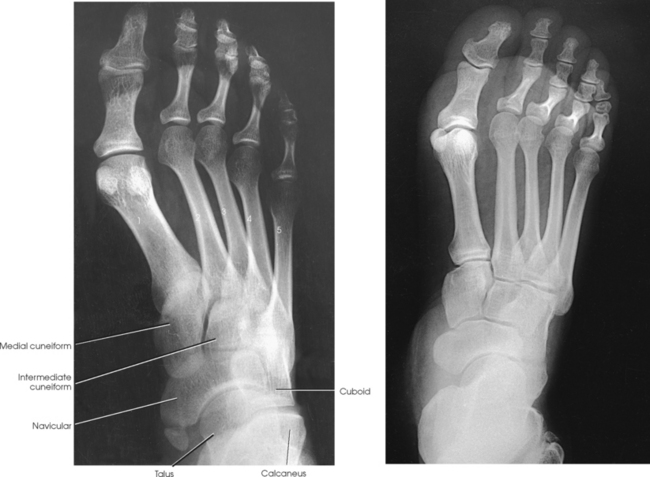

The foot consists of 26 bones (Figs. 6-1 and 6-2):

The bones of the foot are similar to the bones of the hand. Structural differences permit walking and support of the body’s weight. For descriptive purposes, the foot is sometimes divided into the forefoot, midfoot, and hindfoot. The forefoot includes the metatarsals and toes. The midfoot includes five tarsals—the cuneiforms, navicular, and cuboid bones. The hindfoot includes the talus and calcaneus. The bones of the foot are shaped and joined together to form a series of longitudinal and transverse arches. The longitudinal arch functions as a shock absorber to distribute the weight of the body in all directions, which permits smooth walking (see Fig. 6-2). The transverse arch runs from side to side and assists in supporting the longitudinal arch. The superior surface of the foot is termed the dorsum or dorsal surface, and the inferior, or posterior, aspect of the foot is termed the plantar surface.

Beginning at the medial side of the foot, the cuneiforms are described as medial, intermediate, and lateral.

The cuboid bone lies on the lateral side of the foot between the calcaneus and the fourth and fifth metatarsals (see Fig. 6-1). The navicular bone lies on the medial side of the foot between the talus and the three cuneiforms. The cuneiforms lie at the central and medial aspect of the foot between the navicular bone and the first, second, and third metatarsals. The medial cuneiform is the largest of the three cuneiform bones, and the intermediate cuneiform is the smallest.

Structures shown: The resulting image shows an AP (dorsoplantar) projection of the tarsals anterior to the talus, metatarsals, and phalanges (Figs. 6-43 to 6-45). This projection is used for localizing foreign bodies, determining the location of fragments in fractures of the metatarsals and anterior tarsals, and performing general surveys of the bones of the foot.